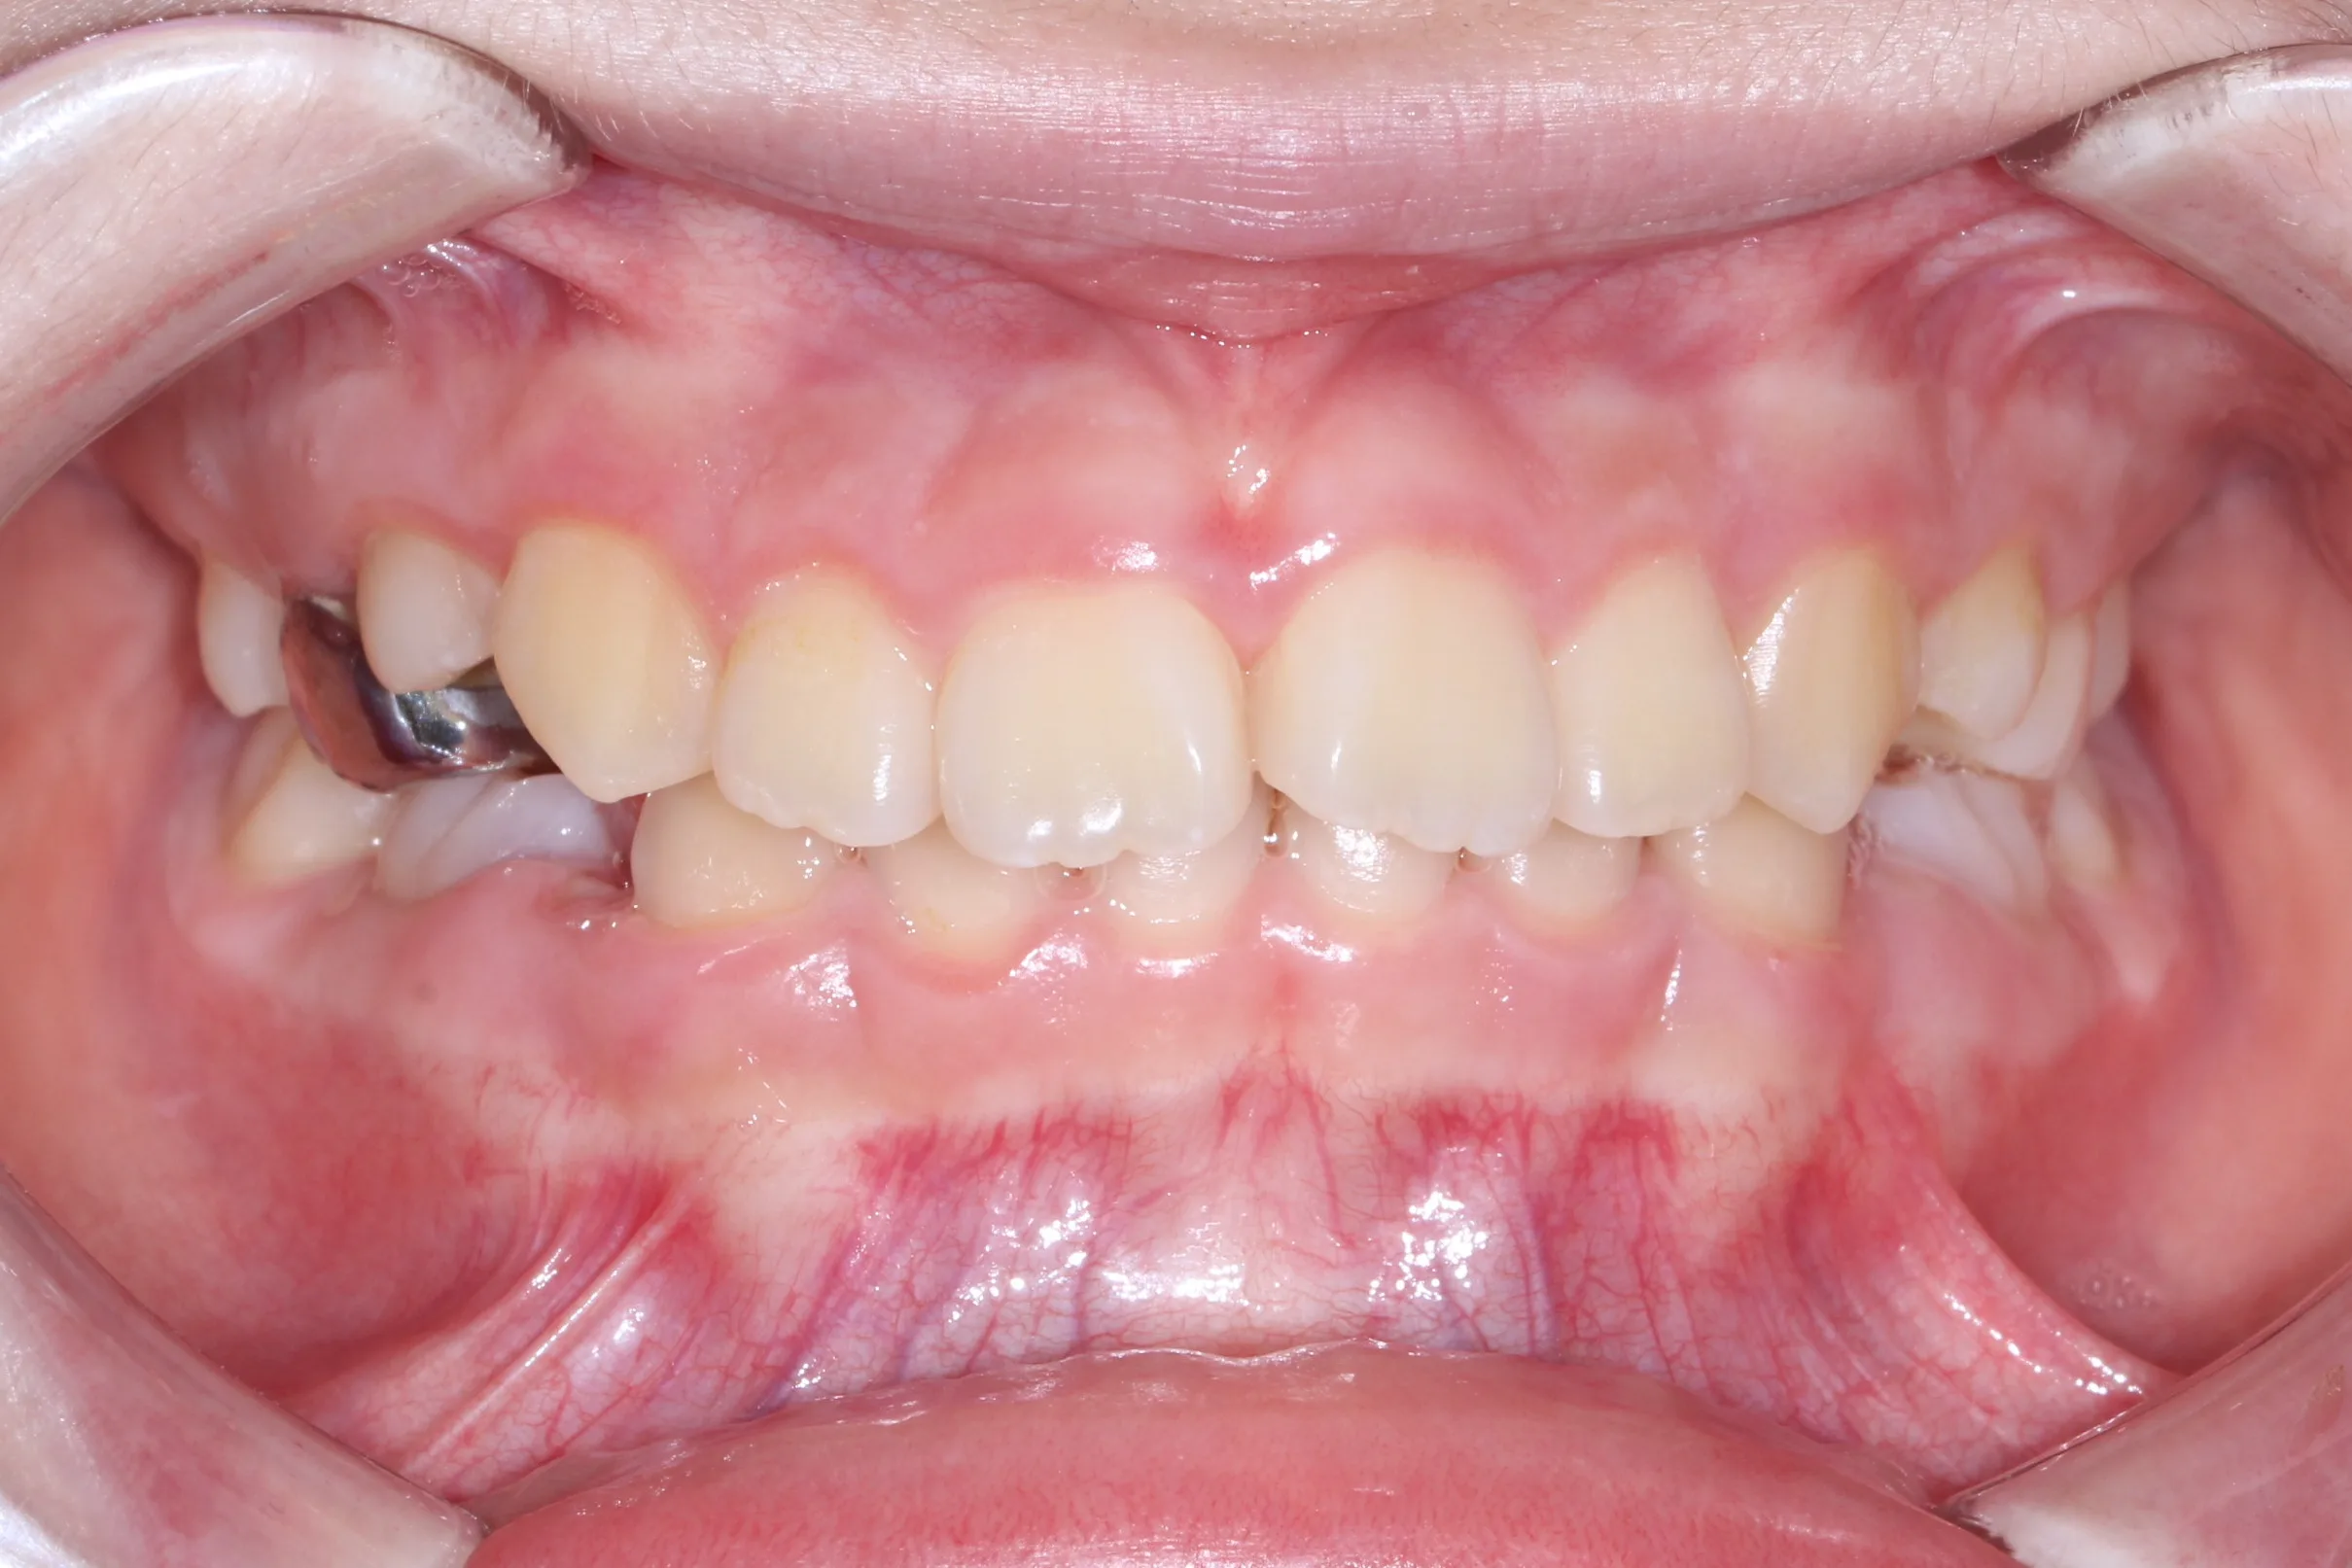

만 11세 환자분께서 튀어나온 앞니와 다물어지지 않는 입술 때문에 내원하셨습니다. 검진 결과 상악 전돌을 동반한 2급 부정교합(Class II malocclusion) 상태였으며, 아래턱의 성장이 다소 부족하여 골격적인 조화가 필요한 상황이었습니다.

이번 치료에는 인비절라인 퍼스트(Invisalign First)에 하악 전방 견인(Mandibular Advancement, MA wing)을 추가하여 치료를 진행하였습니다. 성장기라는 시기적 특성을 적극 활용하여 아래턱의 점진적인 성장을 유도하고, 과도한 상악 전치부 돌출을 개선하는 데 치료의 핵심 전략을 두었습니다.

2년 7개월의 치료 과정을 거치며 환자분의 협조도 덕분에 안모 프로파일과 교합이 안정적으로 개선되었습니다. 성장기라고 해서 무조건 교정이 어려운 것은 아닙니다. 적절한 시기에 맞춤형 장치를 선택한다면 골격적 불균형을 효과적으로 바로잡을 수 있습니다.